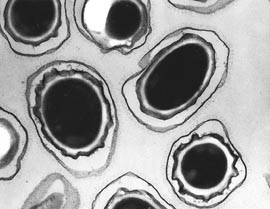

Las esporas del ántrax en una imagen amplificada divulgada por el Pentágono en EE.UU.